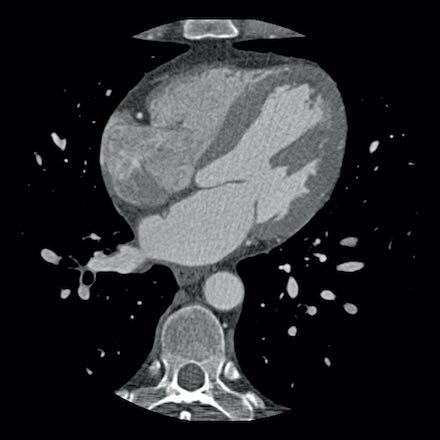

Continue with the next images of the same patient…

Same patient.

Double-oblique (A) and volume-rendered (B) images of the LAD showing the

location and the length of the plaque.

Also, the stenosis in the D2 branch of the LAD can be appreciated on the volume

rendered reconstruction.

Due to the degree of stenosis and the presence of napkin-ring sign (visible on

axial images) this patient underwent ICA where the presence of severe stenosis

was confirmed.